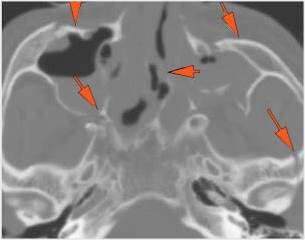

Right Temporal Bone

The external auditory canal shows abnormal soft tissue thickening.

The roof of the mastoid and/or middle ear is fractured.

A possible meningocele and/or encephalocele or CSF leak is present.

The ossicles, in particular the incus long process, the incudostapedial joint and stapes are fractured or dislocated.

The facial canal including the labyrinthine, tympanic and descending portions and nerve are fractured.

The inner ear including the lateral semicircular canals, vestibule and/or cochlea is fractured or otherwise abnormal.

There is subperiosteal, epidural or subdural hematoma along the roof of the mastoid or middle ear or the superior and posterior (intracranial) surfaces of the petrous portion of the temporal bone.

Left Temporal Bone